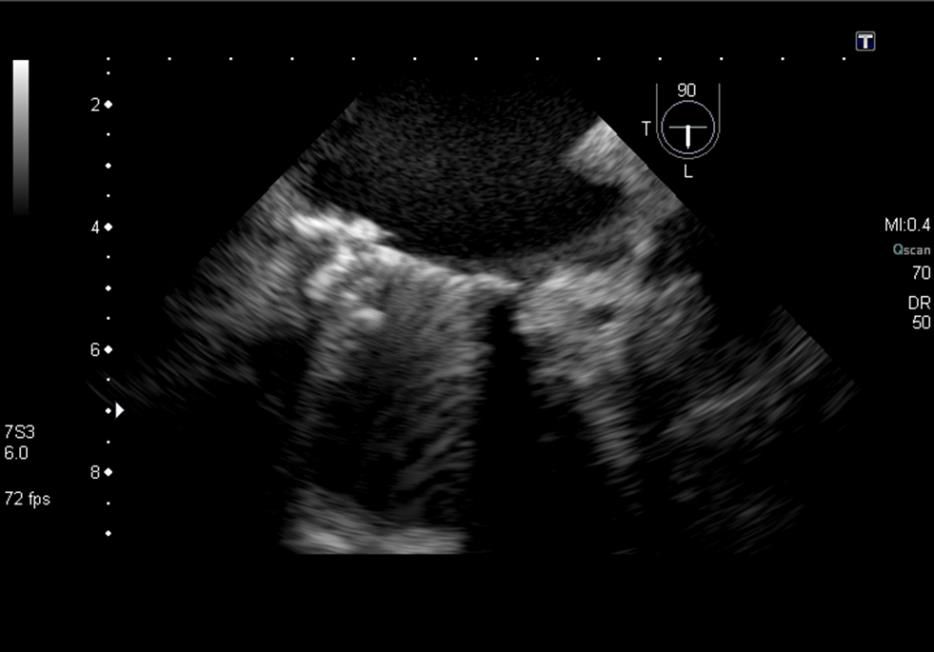

En el caso de nuestra paciente, la sospecha clínica surge a raíz de la presencia de anemia hemolítica a dos años de la cirugía. A través de ecocardiografía transesofágica se detectó la presencia de un leak periprotésico anterior.

Para el implante, realizado en sala de hemodinamia, bajo anestesia general y guiado por ETE, se utiliza un abordaje mixto transapical y retrógrado-transfemoral implantándose exitosamente un dispositivo AMPLATZER Vascular Plug II.